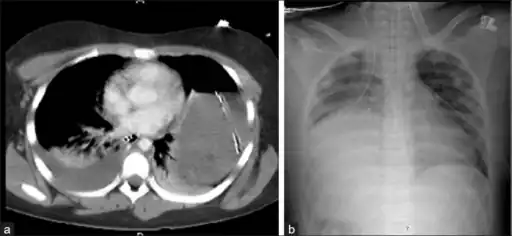

Bilateral blunt diaphragmatic rupture a) confirmation of intrathoracic herniation indicates left hemidiaphragmatic rupture b) post operative image shows elevation of right hemidiaphragm adding suspicion of right diaphragmatic rupture

Bilateral blunt diaphragmatic rupture a) confirmation of intrathoracic herniation indicates left hemidiaphragmatic rupture b) post operative image shows elevation of right hemidiaphragm adding suspicion of right diaphragmatic rupture -